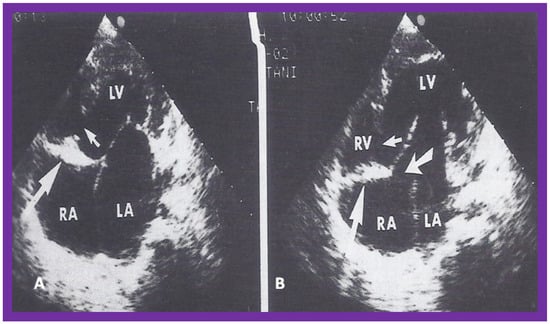

3. Historical Aspects of the Evolution of the Echo of TA

At the time of the preparation of the manuscript for the author’s first edition of the book on tricuspid atresia [23], two dimension (2D) echocardiography was being introduced into clinical practice and the 2D pictures were crude, requiring us to juxtapose line drawings [24] to facilitate interpretation of the figures (Figure 3). The published 2D pictures of TA [25,26], prior to ours, were equally crude. These pictures [24,25,26] represented the state of the art echocardiography machines of that time.

Figure 3. Selected video frames from apical four chamber view of a two dimensional (2D) echocardiographic study, demonstrating a dense band of echoes between the right atrium (RA) and hypoplastic right ventricle (RV). Line drawings are shown beneath the 2D frames. Note that the mitral valve is closed in the left image, while it is open in the right image. The atretic tricuspid valve echoes remain unchanged. LA, left atrium; LV, left ventricle. Reproduced from Reference [24].